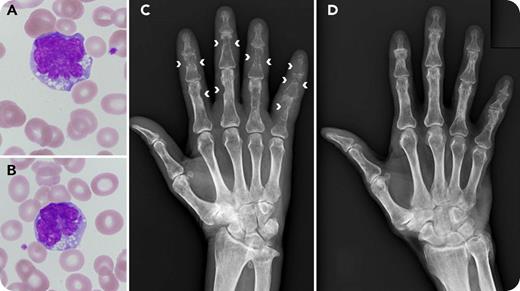

A 68-year-old man with a history of adult T-cell leukemia/lymphoma (ATLL) presented to our outpatient clinic complaining of painful hand swelling of 3 weeks’ duration. Neither enlarged lymph nodes nor skin lesions were observed. The total leukocyte count was normal (5.2 × 109/L) with 3% atypical lymphocytes. The atypical lymphocytes were medium-sized cells with nuclear abnormalities, such as lobulation and notching (panels A-B; original magnification ×1000, Wright-Giemsa stain), and were positive for CD3, CD4, and CD25. The soluble IL-2 receptor level was 17 400 U/mL (normal range, 145-519 U/mL). Radiographs showed multiple subperiosteal bone resorption in the phalanges (panel C; arrowheads).

Subperiosteal bone resorption of the phalanges typically occurs in hyperparathyroidism. Osteoclastic resorption on the periosteal surface gradually proceeds toward the bone center. In our case, serum calcium and intact parathyroid hormone were normal, whereas serum parathyroid hormone–related protein was elevated (1.7 pmol/L; normal range, <1.1 pmol/L). The patient was diagnosed as having relapsed ATLL and received chemotherapy containing the anti-CCR4 antibody mogamulizumab. As a result, rapid relief of the symptoms was obtained. Five months later, the bone lesions also improved (panel D), showing the association of the bone lesions with ATLL disease status. This is the first report of mogamulizumab-sensitive and reversible subperiosteal bone resorption of the phalanges in ATLL.